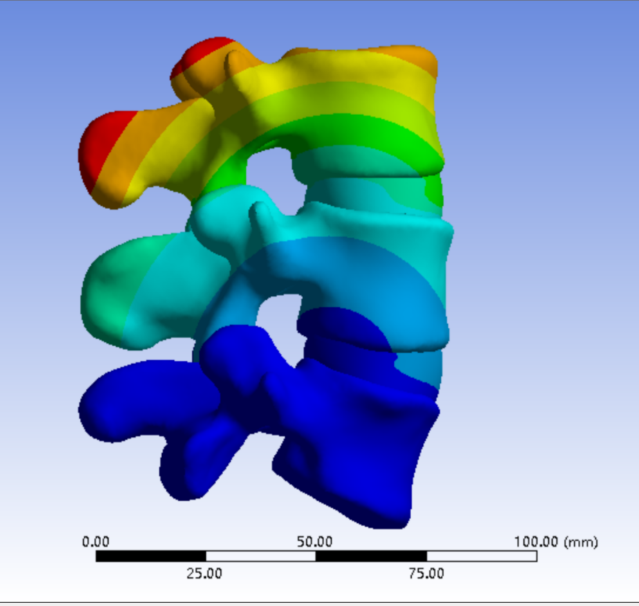

选取一名27岁青年男性志愿者在我院行腰椎螺旋CT扫描�����,扫描平面为���:第十二胸椎椎体至尾椎末端���,扫描厚度为0.625mm���,得到二维断层CT图像489张��,以DICOM格式进行储存���,导入计算机服务器�����。使用Mimics 19.0图像生成和编辑处理软件��,直接读取 DICOM格式的CT扫描数据进行三维重建���,见图 10����。根据软件中不同的灰度值来区分不同的组织����,用 Mimics 软件的阈值分割及区域增长功能画出腰椎(L3-5)����,不同的锥体用不同的颜色区分���,最后用图像填充功能填补图像中的空洞���,接着进行不同部位的三维重建��,得到仅包含骨性结构(L3-5)的模型��。将Mimics 软件得到的模型以STL格式模型文件导入Geomagic wrap2017软件中���,抹去模型钉状物和多余特征��,然后对模型进行优化光滑处理�����,将L3-5光滑处理后的每个锥体进行复制���,再将光滑后的模型在精确曲面中进行网格划分����,并进行构建曲面片及修理曲面片����,最后合成三维实体模型����,见图11�����。此时将复制的每个椎体模型外层向部件内部偏移2mm�����,内部充当松质骨��,外部的则定义为皮质骨����,椎弓根后部统一由皮质骨组成�����。随后将模型以STEP格式文件导入Solidworks2020软件中生成L3-5的实体模型零件��,并在模型零件中构建椎间盘��、髓核����、上下终板和软骨����,完成的实体模型���,此时的模型为单纯的正常腰椎三维几何模型���,各结构并未赋予材料属性与网格划分����,见图12�����。将模型导入ANSYS软件中���,随后对模型中皮质骨���、松质骨���、软骨����、终板���、纤维环���、髓核赋予相应的材料属性赋值���,尽可能地还原各组织材料的生理状况�����,提高模型的可靠性���。定义关节突关节面为 Frictional����,摩擦系数设为0.1��。在connections中建立spring模块���,模拟前纵韧带����、后纵韧带���、黄韧带��、棘间韧带���、棘后韧带���、横突间韧带及关节囊韧带��,各韧带对应刚度赋值��。建立完成后�����,对模型进行mesh操作构建网格���,见图13����。

2���、建立五级成型的有限元模型

正常腰椎模型命名为M0���;0级成型为M1��:不做骨性成型���;1级成型为M2���:软组织成型����,只去除关节囊等部分软组织���,基本不做骨性成型��;2级成型为M3����:少许骨质成型��,不显露下关节突关节面����;3级成型为M4a与M4b���:上关节突尖部(M4a)或上1/2(M4b)去除成型���,显露下关节突关节面����;4级成型为M5�����:上关节突大部分成型或伴有部分椎弓���、峡部或下关节突小部分�����,但预留基底部一部分���,见图16-20���。每组模型都按照前屈����、后伸���、左屈����、右屈���、左旋及右旋6种状态加载��,其他约束条件不变���,观察各组成型对于腰椎活动度及椎间盘应力的影响���。

2����、0-2级成型(M1-M3)因没有进行骨质的切除��,所以对腰椎稳定性没有明显的影响����。3-4级成型时(M4a���、M4b�����、M5)����,L3-4节段在左旋及右旋时的活动度变化最大���,其中左旋由24.15%增加到30.34%����,右旋由27.81%增加到91.42%���,在前屈及左旋时的椎间盘应力值变化最明显���,其中前屈由13.64%增加到31.82%��,左旋由13.33%增加到31.33%��。L4-5节段在后伸时的活动度变化最大��,由46.49%增加到66.96%���,在前屈时的椎间盘最大应力值变化最大����,由19.12%增加到37.50%���,见表3-8��。